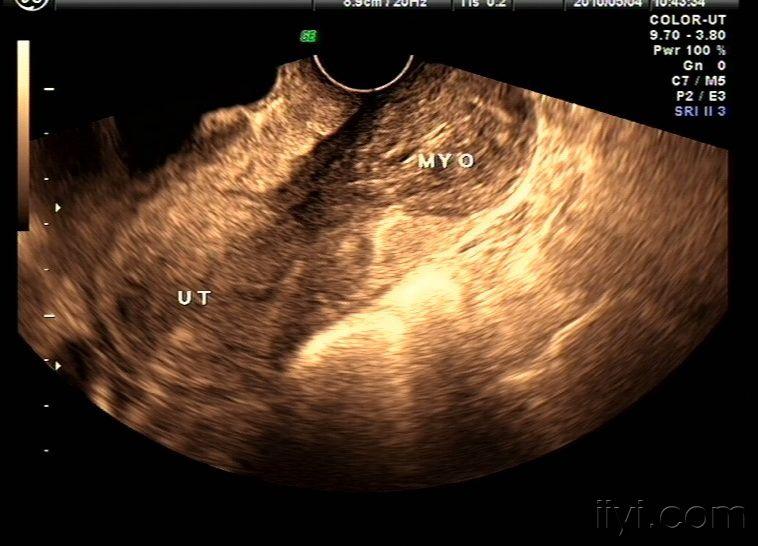

病变晚期可出现远处转移。转移的部位不同,出现的症状也不同,较常见的是锁骨上淋巴结转移,在该部位出现结节或肿块。癌瘤浸润可以通过血管或淋巴系统扩散到远处器官而出现相应部位的转移灶,及其相应症状。四。疼痛。这是晚期宫颈癌的症状。癌瘤沿旁组织延伸,侵犯骨盆壁,压迫周围神经,临床表现为坐骨神经或一侧骶、髂部的持续性疼痛。肿瘤压迫或侵蚀输尿管,管道狭窄、阻塞导致肾盂积水,表现为一侧腰痛,甚至剧痛,进一步发展为肾功能衰竭,以致尿毒症。淋巴系统受侵导致淋巴管阻塞,回流受阻而出现下肢浮肿和疼痛等症状;现在大部分女性患的是常见慢性宫颈炎,约占已婚育龄妇女的一半以上,且它与子宫颈癌的发生有一定的关系。因此,广大女性应对其引起高度重视。宫颈糜烂致癌宫颈炎症、宫颈糜烂是已婚女性的常见病,很大程度都是由分娩、流产或手术操作损伤宫颈,以及产褥期、经期不卫生及细菌感染而导致的。据资料统计表明,因宫颈糜烂发生宫颈癌者比未患此病得宫颈癌者的几率高7~12倍,故发现此病必须认真治疗,直到彻底治愈。子宫肌瘤致癌这是中年女性常见的一种妇科良性肿瘤,越来越有年轻化的趋势。目前这种疾病的病因还不是非常清楚,但与内分泌紊乱有一定的关系。

子宫肌瘤若迅速增大,可压迫直肠、膀胱而引起排便、排尿困难,也有部分人可能演变为恶性肿瘤,这样确诊为子宫肌瘤的人,就应该密切观察和随诊,或及早采取措施,慎防发生恶变。子宫内膜增殖致癌有研究表明,子宫体癌是我国癌症发病率明显上升的病症之一。子宫内膜增殖属一种良性病变,是由于大量雌激素刺激子宫内膜所致,表现为不规则的多量的异常子宫出血。这种病变有演变为子宫内膜癌的可能,所以如果女性一旦发现有这样的病症现象,也应及时到医院检查、治疗。***色素痣致癌***色素痣是发生于***皮肤上的黑色斑点,有的光滑、有的粗糙,有的可有毛发生长。***色素痣比身体其他痣更容易恶变,这是因为***部分常受摩擦和刺激,又因色素痣对性激素的刺激作用较为敏感,往往在青春期和妊娠期增大、变黑。据统计,40%~80%的恶性黑色素瘤都发生于色素痣。妇婴医院的专家建议对***色素痣一定要尽早到妇科进行检查,或进行预防性切除,以防止发生恶变。宫颈癌前病变临床表现宫颈癌前病变患者一般不表现明显症状,或仅有一般宫颈炎的症状,如白带增多。也有主诉白带带血或性接触后少量***流血等。妇科检查可见宫颈光滑,无明显炎症,或有宫颈充血或糜烂,糜烂程度不等,范围也不同,触之有时易出血,与一般慢性宫颈炎无明显区别。